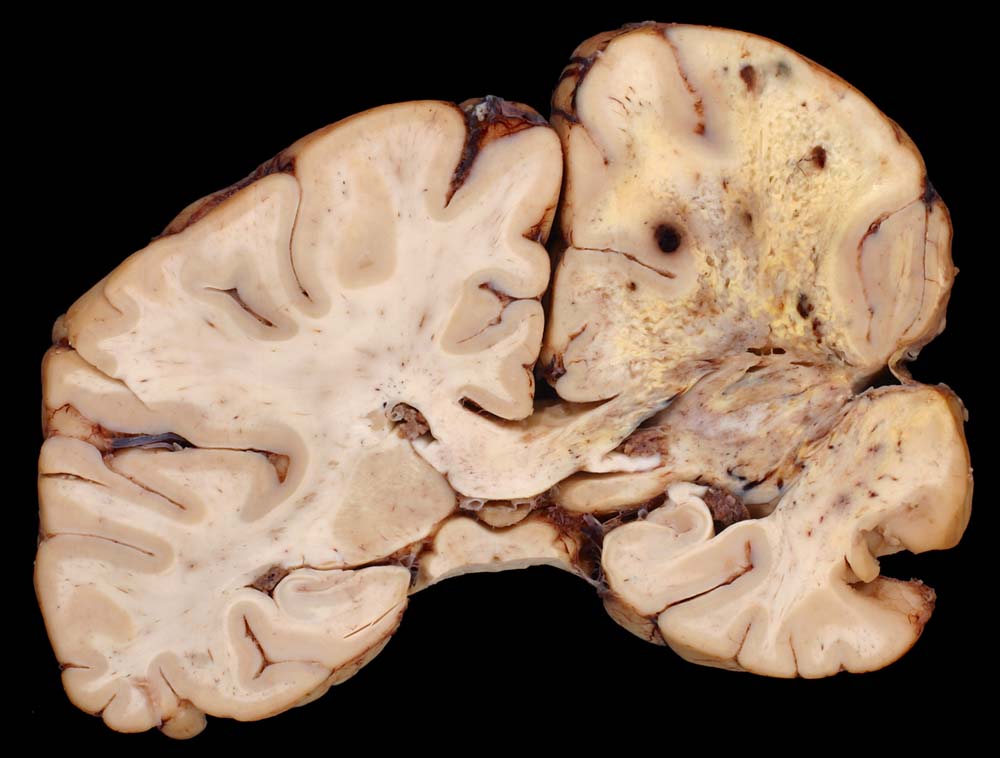

Glioblastoma multiforme (WHO Grad IV)

Sehr unscharf begrenzter Tumor mit bunter Schnittfläche und ausgedehnten Nekrosen.

Glioblastoma multiforme. Resektionen. Radio- und Chemotherapie, Thalidomid-Therapie.

Makroskopie